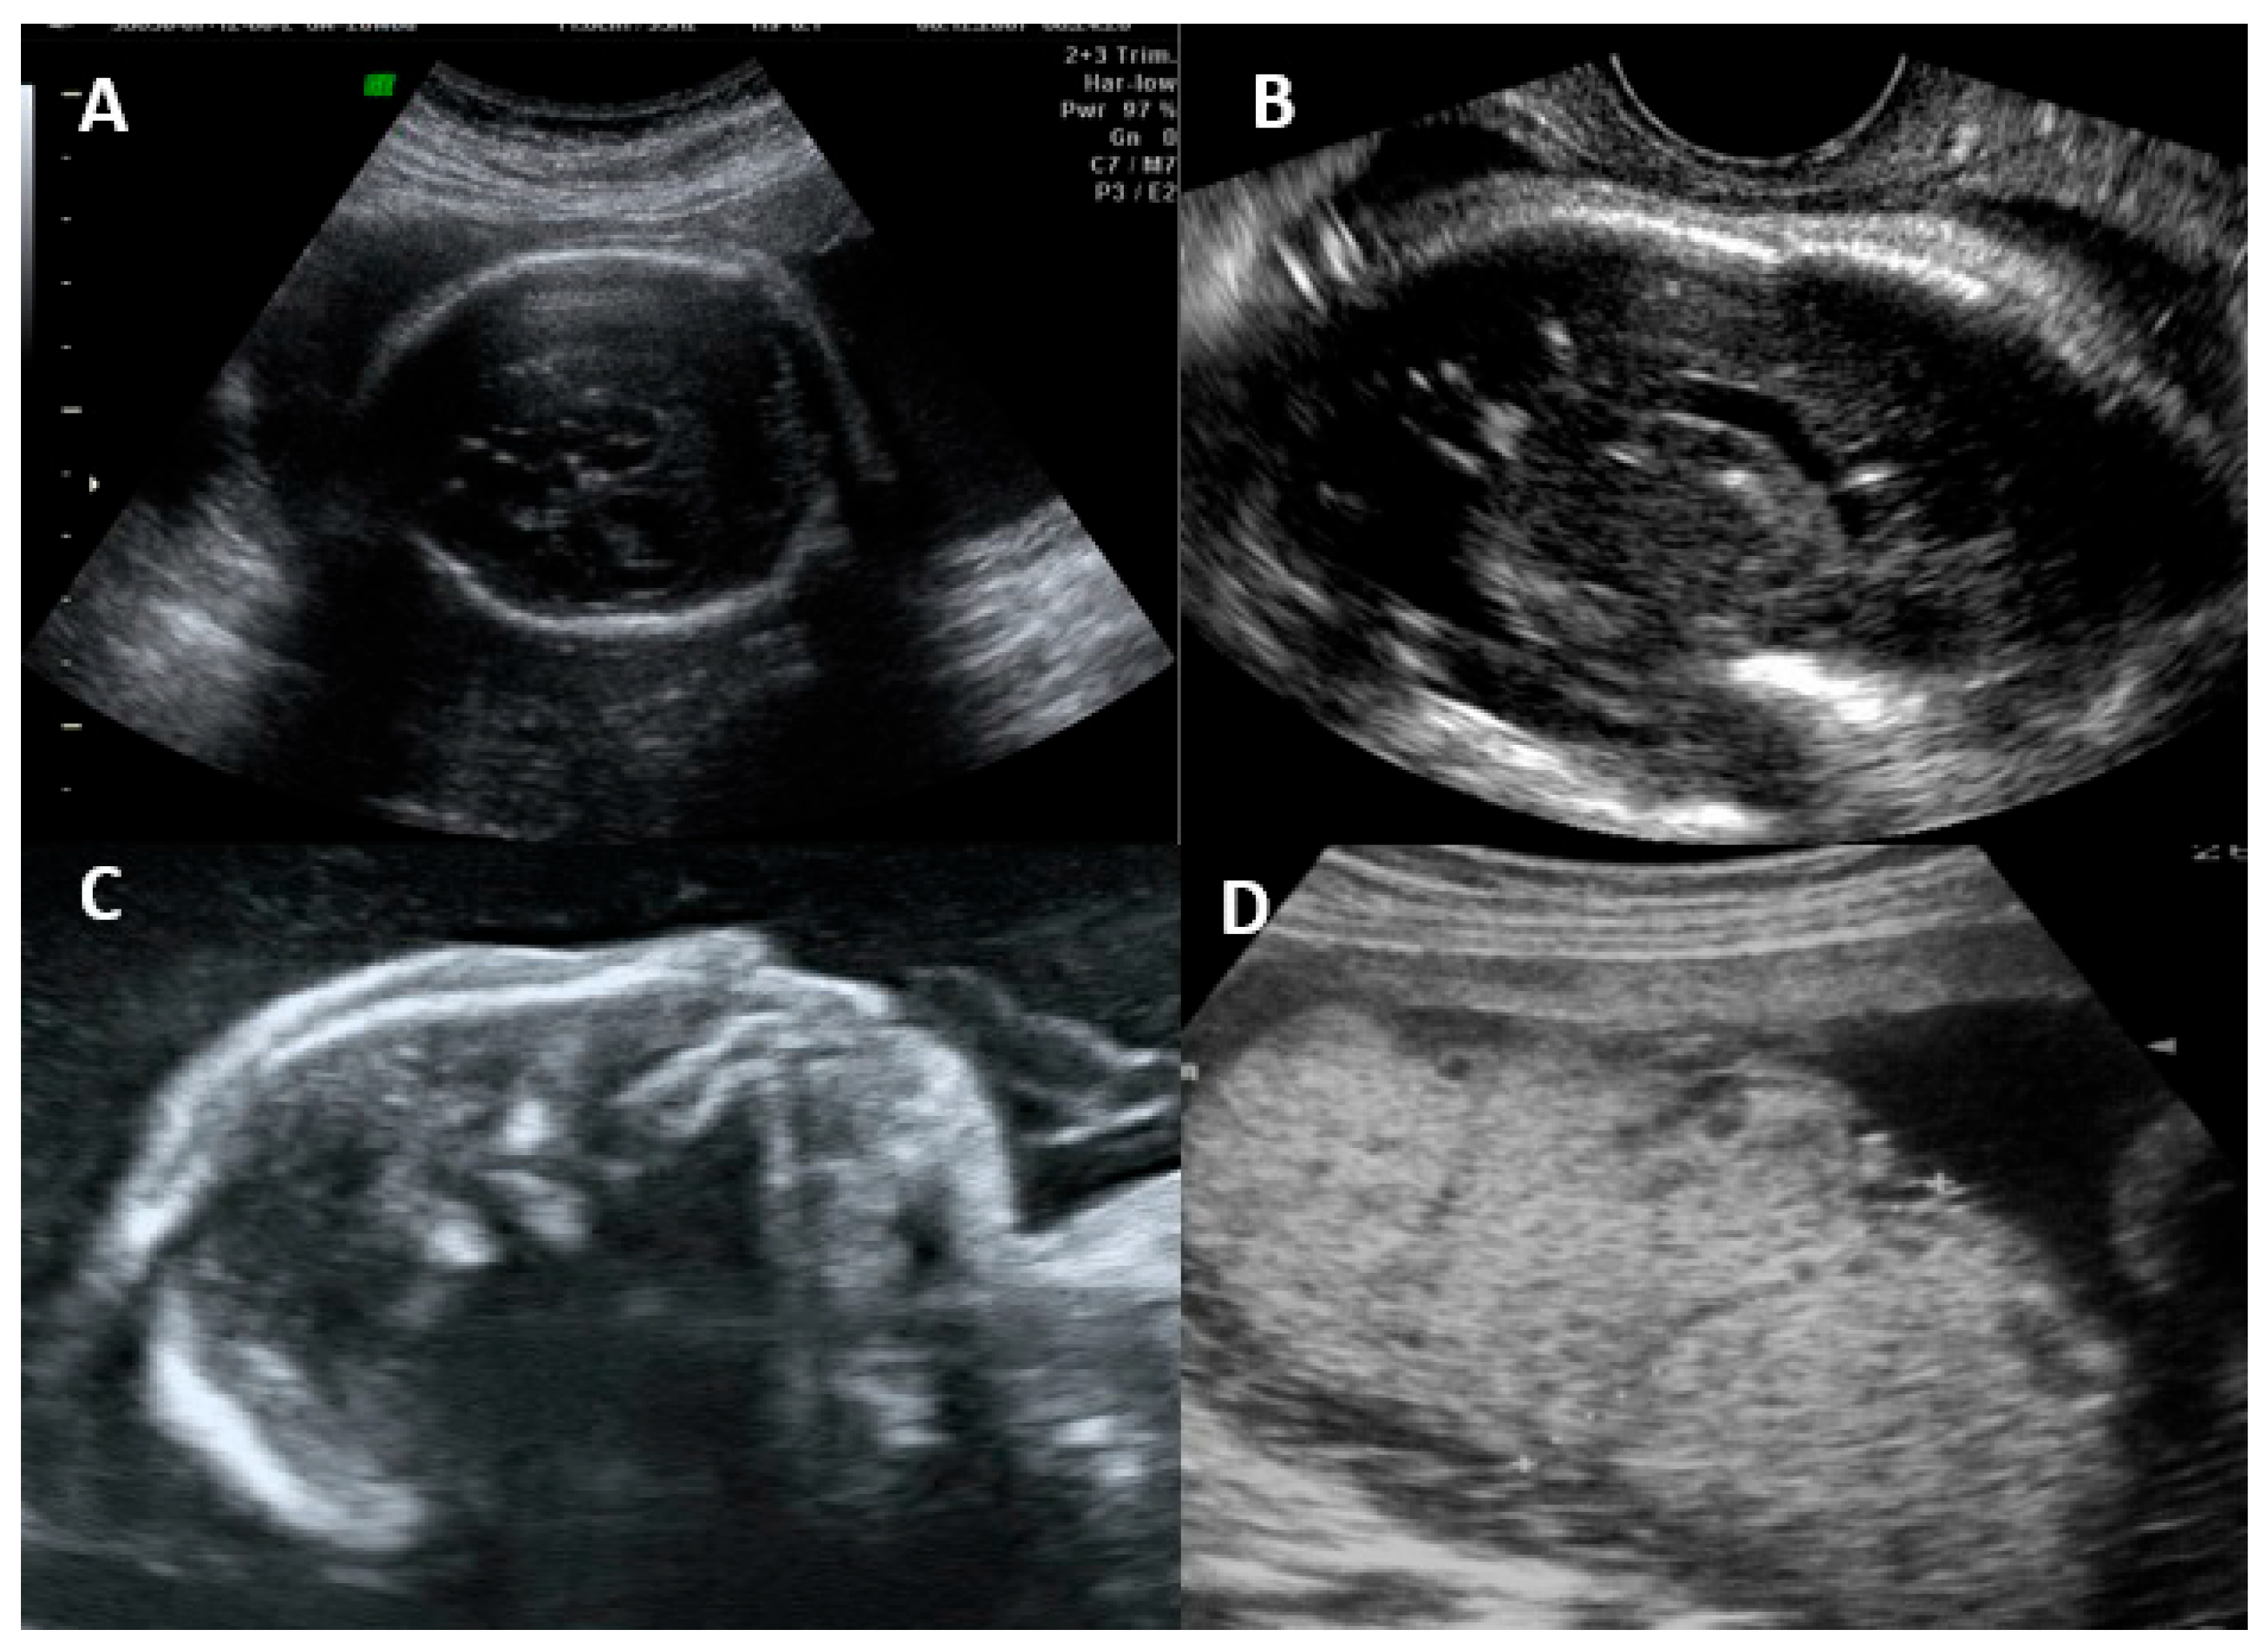

The fetal disease is usually progressive, and the initial symptoms on ultrasonography are usually due to systemic infection (FGR, abnormal amniotic fluid volume, ascites, pleural effusion, skin edema, hydrops, placentomegaly, hyperechogenic bowel, splenomegaly, and hepatic calcifications) [16,55]. CNS findings usually occur after weeks, and severe brain involvement is usually a predictor of poor prognosis, with microcephaly being the only finding that actually predicts an unfavorable outcome in up to 95% of cases [16,25,55]. The most common findings and their classification are summarized in Table 2. Figure 2 shows the ultrasonographic findings regarding intrauterine CMV infection.

Figure 2.

Ultrasonographic findings in a fetus with intrauterine cytomegalovirus infection. (A) Transabdominal ultrasound showing periventricular calcifications. (B) Transvaginal ultrasound showing periventricular calcifications. (C) Microcephaly. (D) Placentomegaly.

Vasculitis is a nonspecific finding described as a candlestick pattern of punctate echogenicity within the brain parenchyma underlying the lateral ventricular rim, along with strands within the ventricle [56]. Hyperechogenic intestine is the most common extracerebral finding, but it is nonspecific and can occur in normal fetuses, those with chromosomal abnormalities, cystic fibrosis, and other infections. Most cases resolve spontaneously; however, fetuses with this finding, even if isolated, should be evaluated and followed [49].

The most common ultrasonographic findings of intrauterine CMV infection are ventriculomegaly, periventricular changes, temporal cysts, and brain parenchymal lesions [25]. Magnetic resonance imaging (MRI) has been shown to complement ultrasonographic imaging in prenatal CMV assessment [25,26]. For example, Buca et al. [26] found that in 6% of ultrasounds in which no CNS abnormalities were seen, the MRIs were positive, but only in cases infected in the first trimester of pregnancy. The abnormalities seen on MRI are the same as those seen on ultrasound, but with a different incidence, with the most common abnormalities seen on MRI being temporal cysts and lesions in the brain parenchyma [25]. (Figure 3) It is known that the additional findings on MRI are due to the lack of studies using multiplanar neurosonography performed by an experienced professional, because when this is method is used, the results of both types of imaging are similar [26,27]. Intrauterine CMV infection is an indication for multiplanar (transvaginal) neurosonography [27]. The main changes seen on neurosonography are abnormal patterns of periventricular echogenicity (suggesting periventriculitis), ventriculomegaly, and echogenic focus in the brain parenchyma [27].